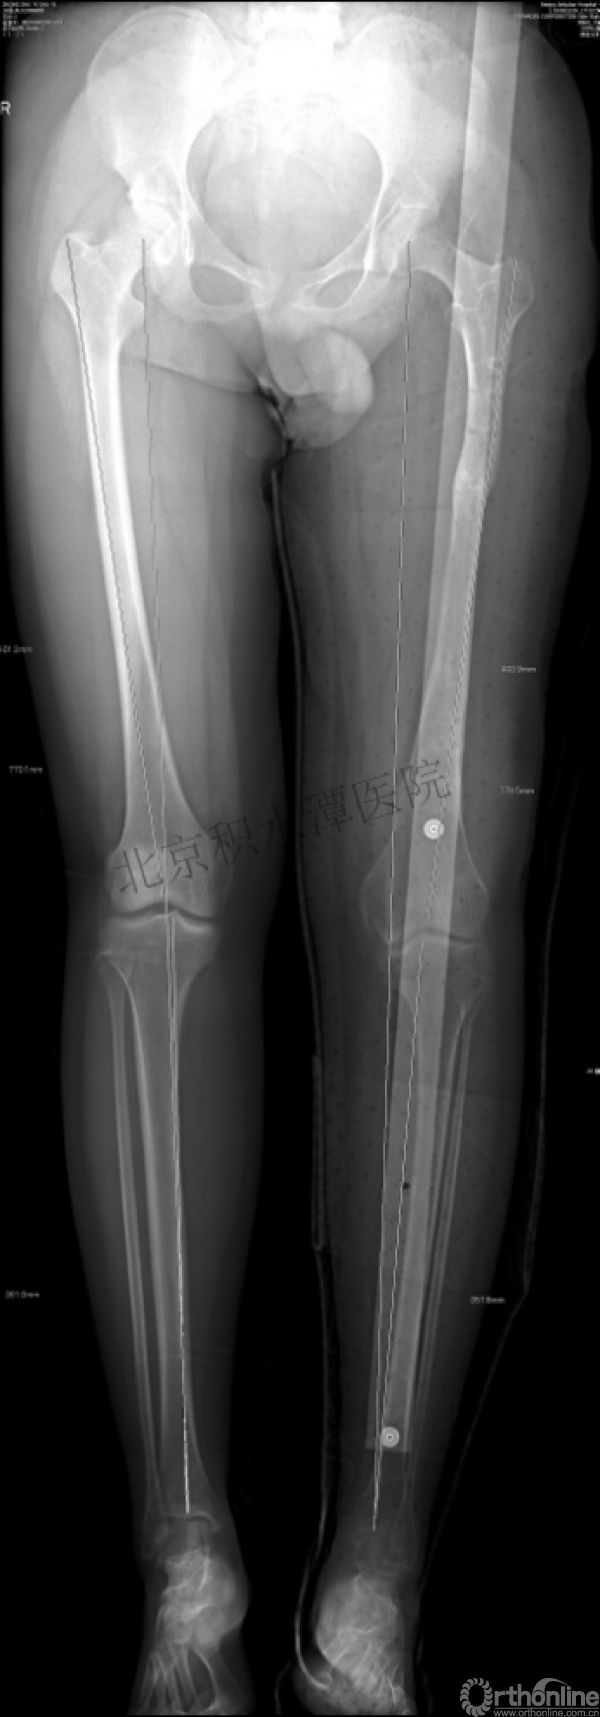

病例分享四

女孩、8岁,桡骨远端骨折

原始损伤

伤后1个月

伤后14个月

病例分享五

女孩、6岁,股骨干骨折

牵引后4周

伤后18月

没有任何外观和功能障碍!相信每位小儿骨科医生都会有很多类似的病例!除非您不承认或者没有认识到塑形!

儿童骨折的基本特点—塑形!

1.充分利用此特点

2.不要人为地破坏

3.不要好心办坏事